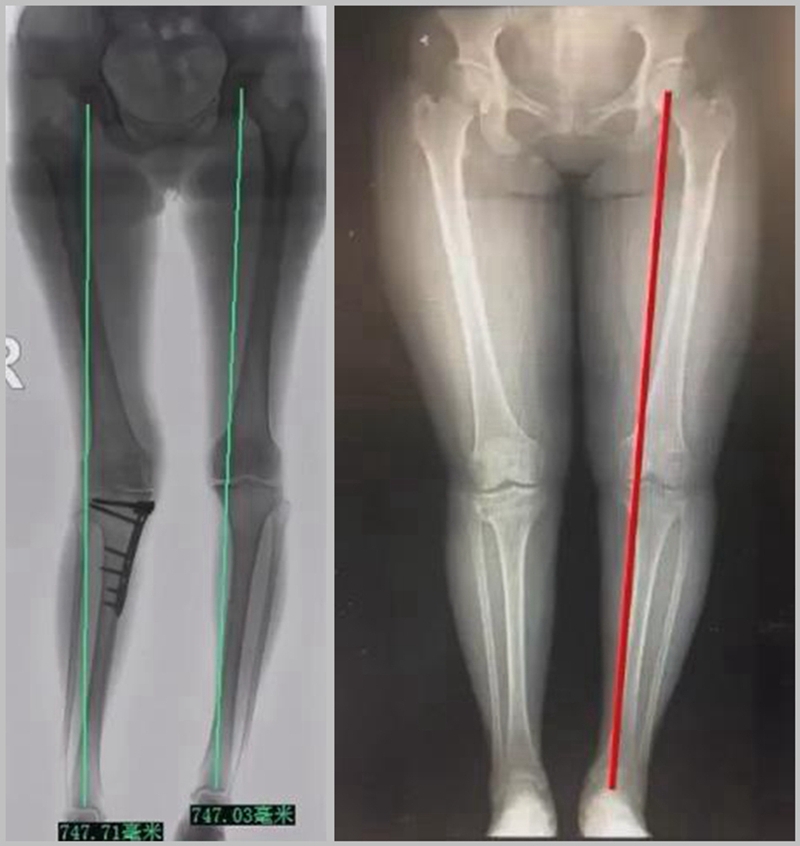

二、矫正不良

截骨实际上是通过力线的重新分布来调整好关节的压力,但是经常会出现矫正过度或者矫正不良的问题。

1、综合判断力线的方法

现在对于力线的判断大致通过以下几方面:①大体形态;②透视确定力线,连接股骨头中心、踝关节中心,看力线杆和膝关节中心的位置关系;③MPTA(胫骨平台关节线和胫骨侧机械轴夹角);④PSI。

1、原因及预防

(1)肢体外旋

一般来说在麻醉状态下肢体会处于外旋位,此时去测定力线的话往往需要将肢体放在旋转中立位,但是在内旋肢体的过程中会出现内翻应力,那么这种情况下判断力线会带来误差,所以通常建议大家要把手术床做一点旋转,让患肢处于自然的旋转中立位,这样再去判断力线就比较准确。

(3)力线验证未模仿负重应力

现在所谓的目标力线应该是模仿负重时的力线。做截骨时,通常会将力线轻度外移,如果没有考虑关节内畸形、韧带松弛或是软骨磨损,那么在负重时,在内侧副韧带撑开过程中,会出现力线偏移。所以要注意,手术中间在调整目标力线时,要以应力状态下为标准。

矫正不良与肢体位置、MCL浅层松解不够、力线验证及拉力螺钉加压过度有关。

要注意术前放置肢体于中立;MCL浅层彻底松解;外翻应力下验证力线;合理的拉力螺钉加压;及时处理发生的矫正不良。